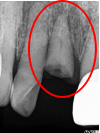

Before

破折した部分を取り除いたところ

After

根管治療後